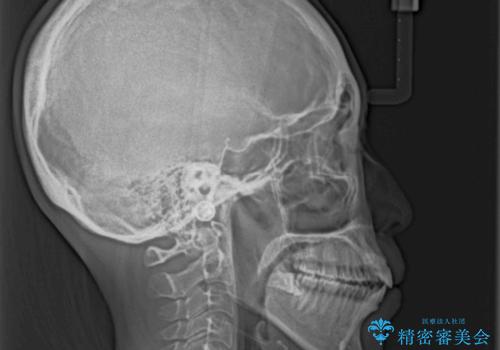

- 上下前歯の隙間と口元の出っ張った感じを気にして来院された患者様です。

上下の隙間は舌突出癖によるもので、またその癖により前歯が前方に出ている状態でした。

口元の出っ張りを改善するため、上下左右第一小臼歯4本を抜去し、ワイヤー装置にて矯正治療を行うこととしました。